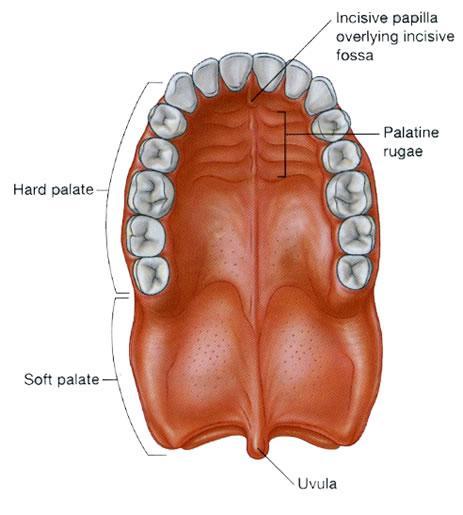

Oral Cavity (Buccal)

Hard Palate

Soft Palate

Rugae of the Hard Palate

Uvula